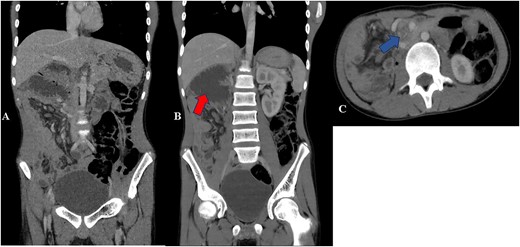

Contrast CT abdomen—coronal (A and B) and axial views (C) show small bowels on the right side of the abdomen and the large bowels on the left side of the abdomen. Image B shows distended duodenum (red arrow). Image C shows twisting of the mesentery and the superior mesenteric artery giving whirlpool sign appearance (blue arrow).

His laboratory results revealed a normal leucocyte count and hemoglobin of 12.2 g/dl. His serum sodium was 122.40 mmol/l and potassium was 2.57 mmol/l. Renal and liver function tests were within normal range as well as serum albumin and total protein. His abdominal ultrasound was normal. His esophageal-gastro-duodenoscopy showed normal mucosa with 2 l of bilious contents in the stomach; however, no obvious obstruction seen. His abdominal–pelvic computed tomography (CT) scan showed a severely dilated duodenum with a transition point at the superior mesenteric artery. Twisting of the mesentery seen around the superior mesenteric artery with ‘Whirlpool sign’ (Fig. 1). These features suggestive of midgut volvulus.

Midgut malrotation in adults may present as an acute abdomen that requires urgent intervention but may also present in non-acute setting with non-specific and chronic symptoms as our case, which include intermittent abdominal pain, bloating and food intolerance hence leads to increased morbidity and mortality [3]. This unspecific features cause delay in diagnosis similar to our case [3]. The acute features include midgut volvulus, small bowel obstruction and bowel ischemia [3]. Upper gastrointestinal series with oral contrast is the test of choice in the pediatric group along with Doppler ultrasound of the SMA; however, currently contrasted CT scan is the modality of choice showing ‘whirlpool’ sign as seen in Fig. 1 [4].